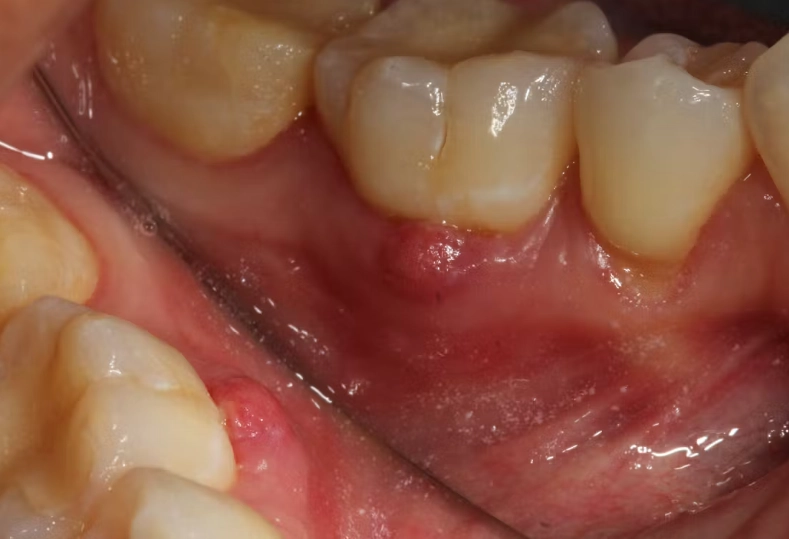

You can't always feel the abscess itself because it's buried in your jawbone. But the sinus tract? That's the visible or palpable clue. Here's what people typically notice:

- A Recurring "Pimple" on the Gums: This is the hallmark. It's a small bump, often red or yellow-ish at the tip. It might burst and release a bad-tasting, salty fluid (that's the pus), then seem to heal, only to come back days or weeks later. This cycle is a dead giveaway.

- The Gutta-Percha Test: This is a classic move. The dentist might take a very thin, flexible point (called a gutta-percha point) and gently insert it into the opening of the sinus tract. Then they take an X-ray. The point will often show up on the X-ray tracing a path directly to the culprit root tip. It's like following a road map to the problem.

Putting all this together—the bump, the tooth history, the clinical tests, and the X-ray evidence—confirms a diagnosis of a chronic periapical abscess with a draining sinus.